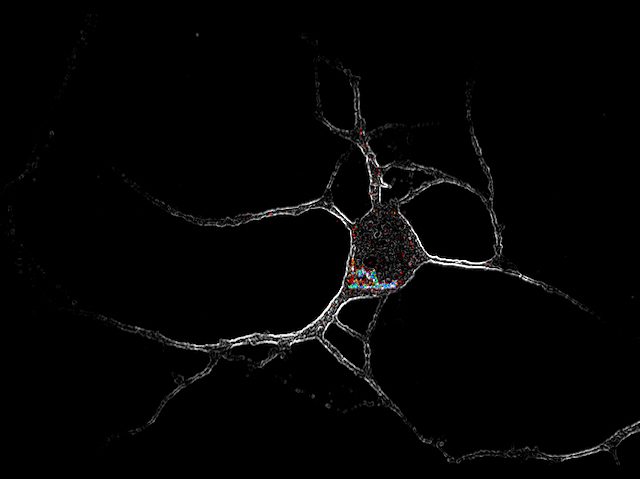

Where would you expect to find psychedelic drugs? A nightclub, a back alley, or a hospital? Expectations are changing, thanks to increased research into their mechanisms of action and potential as treatments of those mental health conditions that are characterised by a loss of brain cell connections such as PTSD and depression. Previous studies had identified that they help rebuild these connections, and that they interact with a particular group of receptors on neurons, called 5-HT2ARs (coloured inside a white highlighted neuron, pictured), which serotonin also binds to. But it wasn’t clear how the drugs’ binding causes neuron growth while serotonin’s does not. A new study showed this outcome only happens when binding happens inside nerve cells, not on the surface, which is where serotonin interacts. This detail may be a key feature to bear in mind when developing much-needed treatments for people with severe mental health conditions.